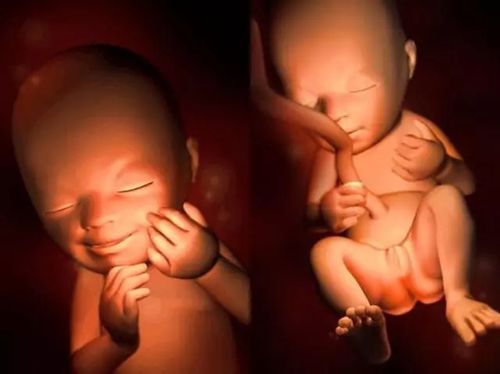

胎儿发育过程图,给大家看看各段时间胎儿的发育图,从怀孕第一周到分娩

好神奇,胎儿在妈妈肚子里是这样一点一点长大的!